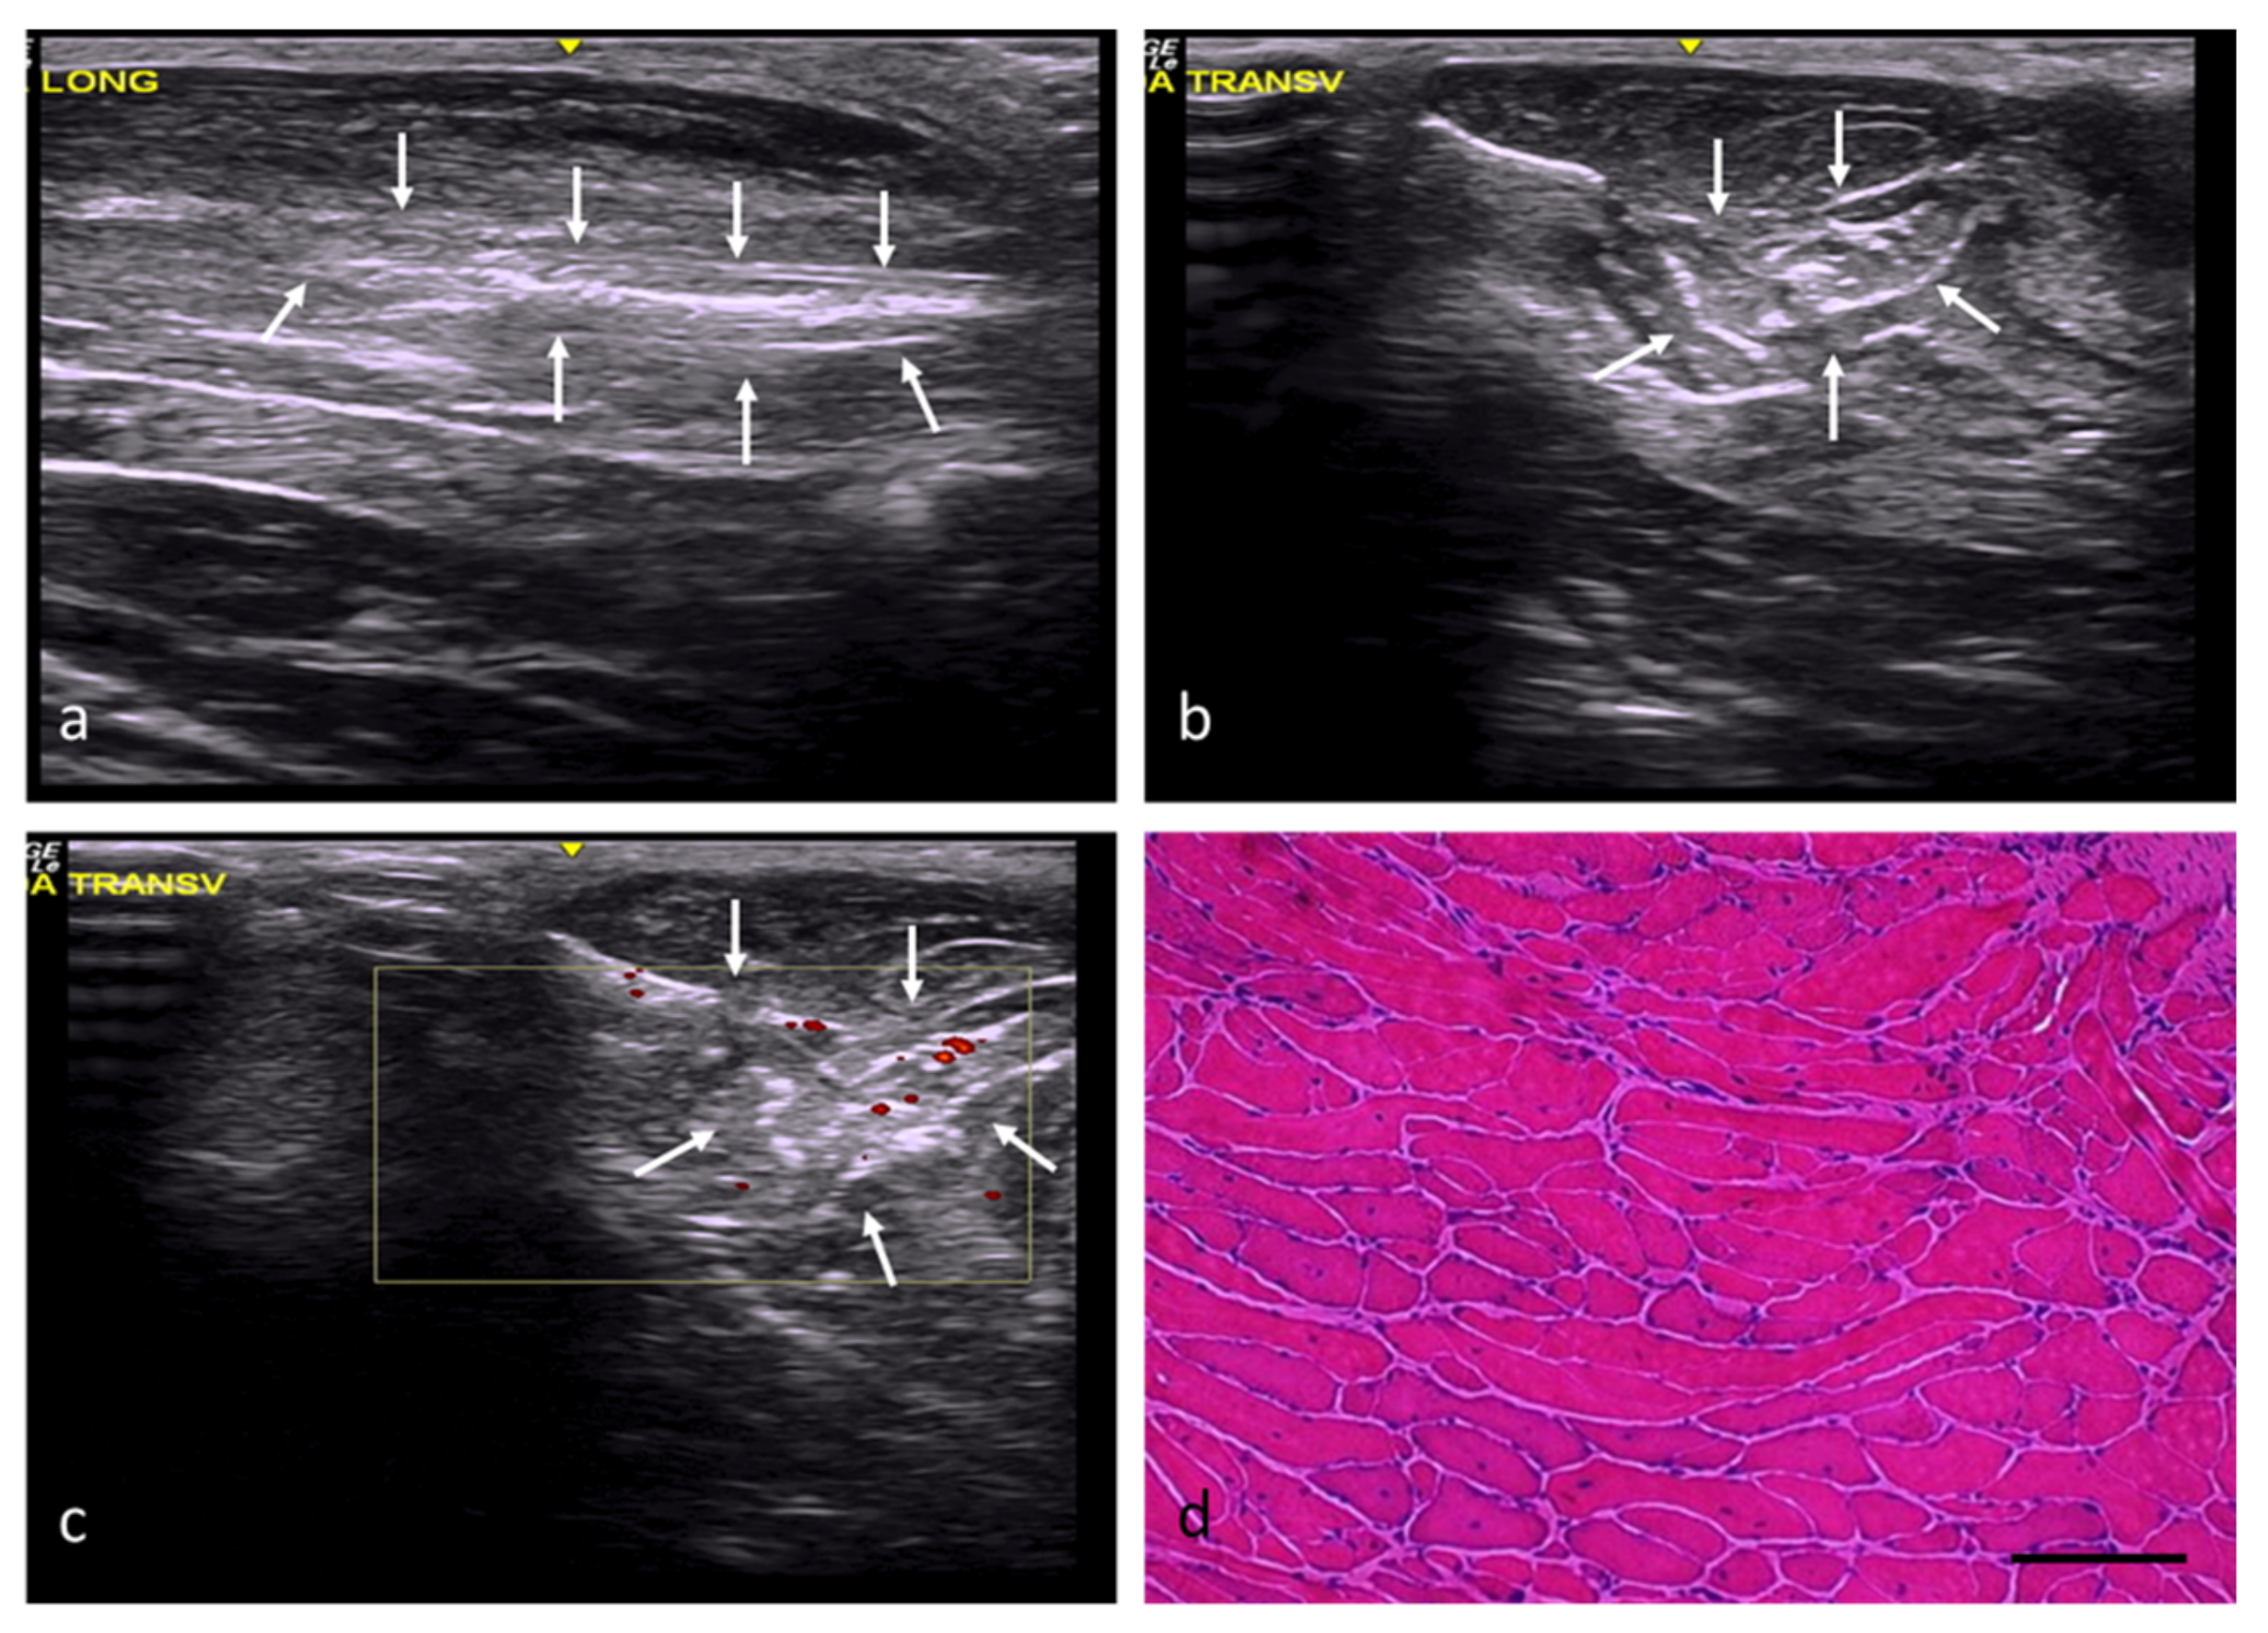

In the adipose tissue (AT) group, the injury margins were slightly unclear, although the implantation areas were hyperechogenic and had a slightly distorted echostructure (Figure 4a–c). According to the histological study, the adipose tissue implanted in the defects had been mostly replaced by skeletal muscle tissue (Figure 4d), with a percentage of fibrosis of approximately 20%. The newly formed muscles exhibited variations in terms of the orientation and size of their fibers, with some being large and others clearly atrophic, but all of them with central or internal nuclei (Table 2).

Figure 4.

AT group. (a) Longitudinal axis, with images of a hyperechoic injury with poorly defined margins, an imprecise morphology, and a slightly distorted echostructure, demarcated by white arrows. (b) Transverse axis, with images of an injury with slightly increased echogenicity, poorly defined margins, and an imprecise morphology. (c) Transverse section assessed by power Doppler imaging, with images of slightly increased intralesional vascularization. (d) Transverse section representative of the muscle histology. H-E. Size scale: 100 µm.

In the Osteovit® (OS) and heterologous decellularized muscle matrix (DM) groups, the injury margins were well defined, and the injury area had a variable morphology. In both cases, the echogenicity was increased and the echotexture severely distorted (Figure 5a–c, Figure 6a–c). In the OS group, the percentage of fibrosis reached approximately 31%. However, although the implantation of the scaffold in this group did not prevent the generation of new muscle fibers, most of these fibers exhibited atrophic histological and histomorphometric features secondary to denervation (Figure 5d). The connective tissues’ thickness contained complete bundles of atrophic fibers, some of which were found to coexist with very large fibers (suggestive of reinnervation). The muscle fibers reached maturity in certain areas where reinnervation of the regenerative muscle fibers was not impeded, albeit with some morphological abnormalities with regard to their shape and size.

Figure 5.

OS group. (a) Longitudinal axis, with images of a well-defined injury with increased echogenicity and a clearly distorted echostructure compared with the adjacent tissue. (b) Transverse axis, with images of an oval injury with well-defined margins. (c) Transverse section assessed by power Doppler imaging, with images of slightly increased perilesional vascularization. (d) Transverse section representative of the muscle histology. H-E. Size scale: 100 µm.